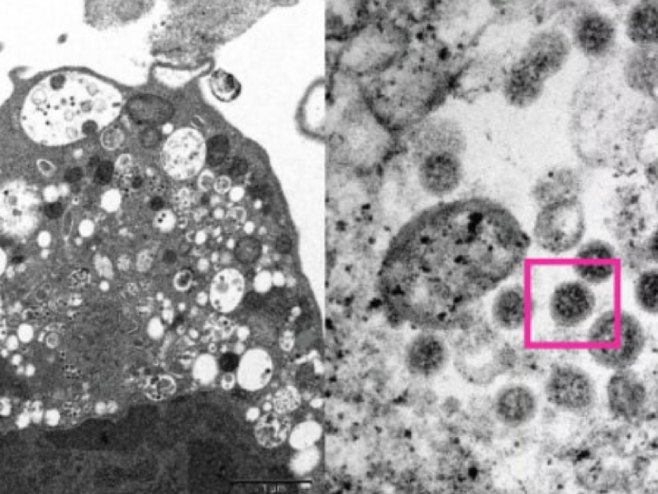

Naučnici medicine, uključujući patologe i virusologe, uspjeli su da naprave elektronski mikrosnimak ćelije bubrega majmuna /Vero E6/ nakon što je zaražen varijantom omikron.

Univerzitet je objavio slike sa malim i velikim uvećanjem.

Pri malom uvećanju, slika pokazuje oštećenje ćelija sa otečenim vezikulama koje sadrže male crne virusne čestice, objasnili su istraživači. Veliko uvećanje pokazuje agregate virusnih čestica sa šiljcima u obliku korone na njihovoj površini.